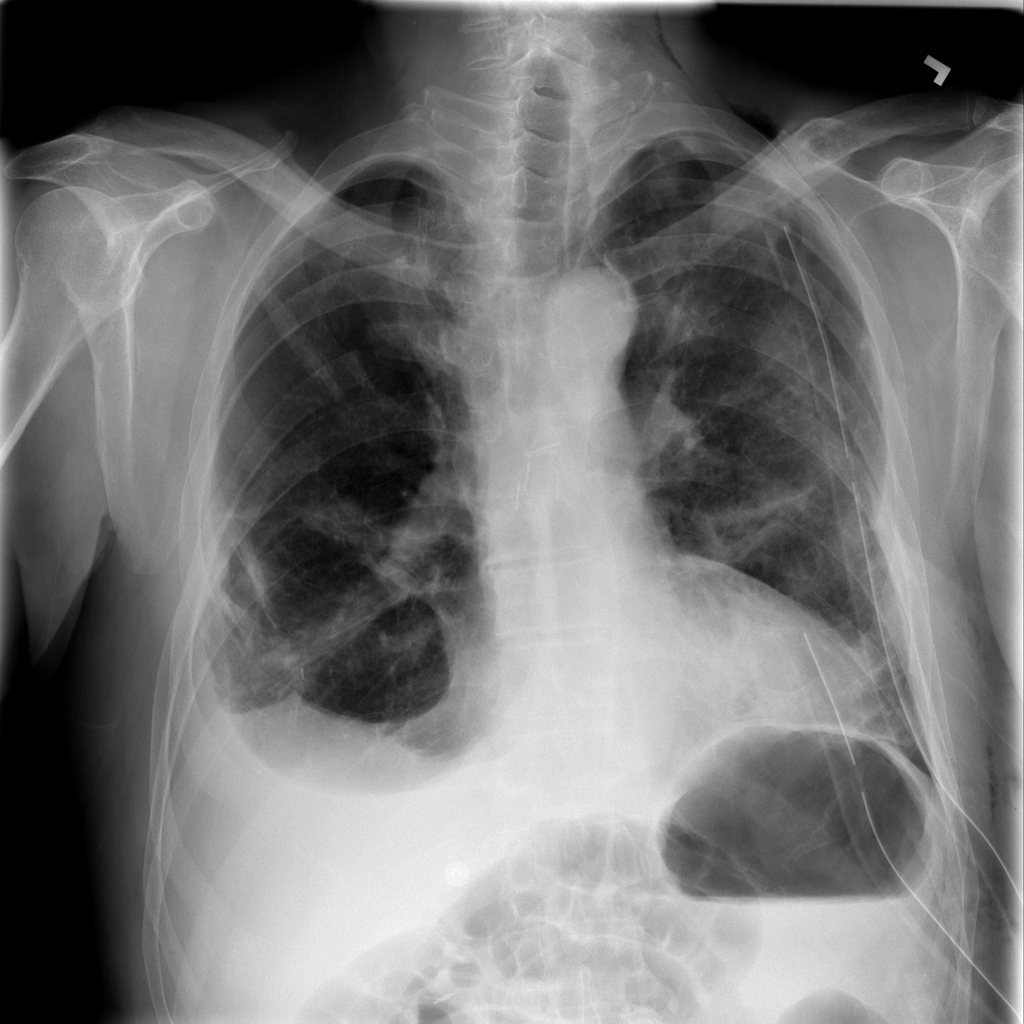

PAT-4639 · IMG-013Pneumothorax

PAT-4639 · IMG-013

AP